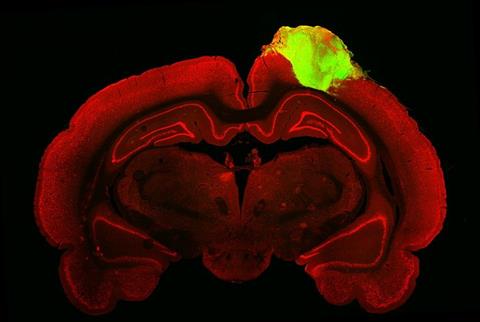

This is a histological image of a rat brain with a grafted human brain organoid [Credit: Jgamadze et al].[/caption]

The researchers cultivated human stem cell-derived neurons in the lab for around 80 days before grafting them into the brains of adult rats that had sustained injuries to their visual cortex. Within three months, the grafted organoids had integrated with their host’s brain: becoming vascularised, growing in size and number, sending out neuronal projections, and forming synapses with the host’s neurons.

The team made use of fluorescent-tagged viruses that hop along synapses, from neuron to neuron, to detect and trace physical connections between the organoid and brain cells of the host rat. “By injecting one of these viral tracers into the eye of the animal, we were able to trace the neuronal connections downstream from the retina,” said Chen. “The tracer got all the way to the organoid.”